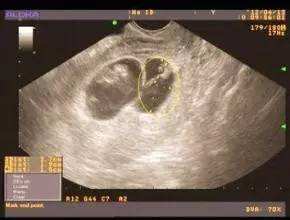

在所有测排卵的方法中,准确的就是B超监测法,它不仅可以测出两侧卵巢中是否有优势卵泡,同时还能测出优势卵泡的大小、子宫内膜的厚度等。此外,这种方法还可以在一定程度上帮助预测排卵和指导受孕性生活。>>>测排卵的时间?点击咨询专家

B超监测排卵需要连续进行。一般情况下,自月经周期的第10天起开始监测,观察卵泡直径的变化。在排卵前4天的卵泡直径平均每日约增3mm,在排卵前卵泡成熟约17~25mm,排卵后卵泡消失,连续监测可见在排卵前卵泡不断长大,当卵泡消失时,提示发生排卵。通常每2天B超监测1次,当发现卵泡直径达17毫米时,应该改每天监测1次。>>>如何知道自己有没有排卵?点击咨询专家

在所有测排卵的方法中,准确的就是B超监测法,苏州东吴中西医结合医院利用高分辨的实时超声已广泛应用于卵泡发育及排卵的形态学检查。超声监测的无创、可动态观察卵泡的发育是其优势。也是监测卵泡更直接的方法。在月经周期中,通过仪器可看到卵泡有小到大,由大到无。真真正正的眼见为实,准确无误。测排卵什么时候合适?点击咨询专家